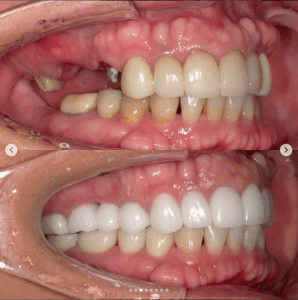

審美歯科症例集(ビフォーアフター)

より多くの症例をこちらのページでご紹介しておりますので、合わせてご覧ください

Case022

口腔内を全体的に治療させて頂いた患者様の症例です。

もともと透明感の無い大きなセラミックが入っていた前歯に、透明感がありスマートな形のセラミックを入れました。また、歯茎のラインにも違和感があったため、今回の治療で治しています。

セラミックと歯茎の境目が綺麗になるかどうかは歯科医の腕次第ですが、とても綺麗にできたと思います。

また、インプラントなどで奥歯の噛み合わせも治療いたしました。

前歯の審美性にご満足いただき、以前より食事がしやすくなったとお褒めの言葉を頂きました。

当院では噛み合わせなどの機能面や審美性を考えた上での全体的な治療が可能です。